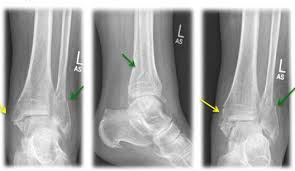

Fraktur oberhalb der verletzen Syndesmose Membrana interossea häufig auch rupturiert Die Maisonneuve-Fraktur wird als Sonderform der Sprunggelenksfraktur auch als Weber C klassifiziert. This normally takes approximately 6 weeks to heal. Die Weber-Klassifikation eine Methode zur Beschreibung von Sprunggelenksfrakturen.

KLASIFIKASI FRAKTUR WEBER Drsimon ponco septiono f Weber A Garis fraktur berada dibawah syndemiosis thibiofibularis f Weber B Garis fraktur berada setinggi syndemiosis thibiofibularis f Weber C Garis fraktur berada diatas syndemiosis thibiofibularis f. Weber C Fraktur immer Weber A- und Weber B- Frakturen mit. Many translated example sentences containing Weber c Fraktur English-German dictionary and search engine for English translations.

Weber C Fraktur. Neben der Weber C Fraktur gibt es auch noch die Fraktur der Klasse A und B. Was ist eine Weber-C-Fraktur. DayZ sa well kit DayZ Expansion Building Kits - YouTub. Verschobenem Bruch dislozierte Fraktur undoder. It has a role in determining treatment. Weber C Fraktur. Look up the French to German translation of weber c fraktur in the PONS online dictionary. The Weber ankle fracture classification or Danis-Weber classification is a simple system for classification of lateral malleolar fractures relating to the level of the fracture in relation to the ankle joint specifically the distal tibiofibular syndesmosis.